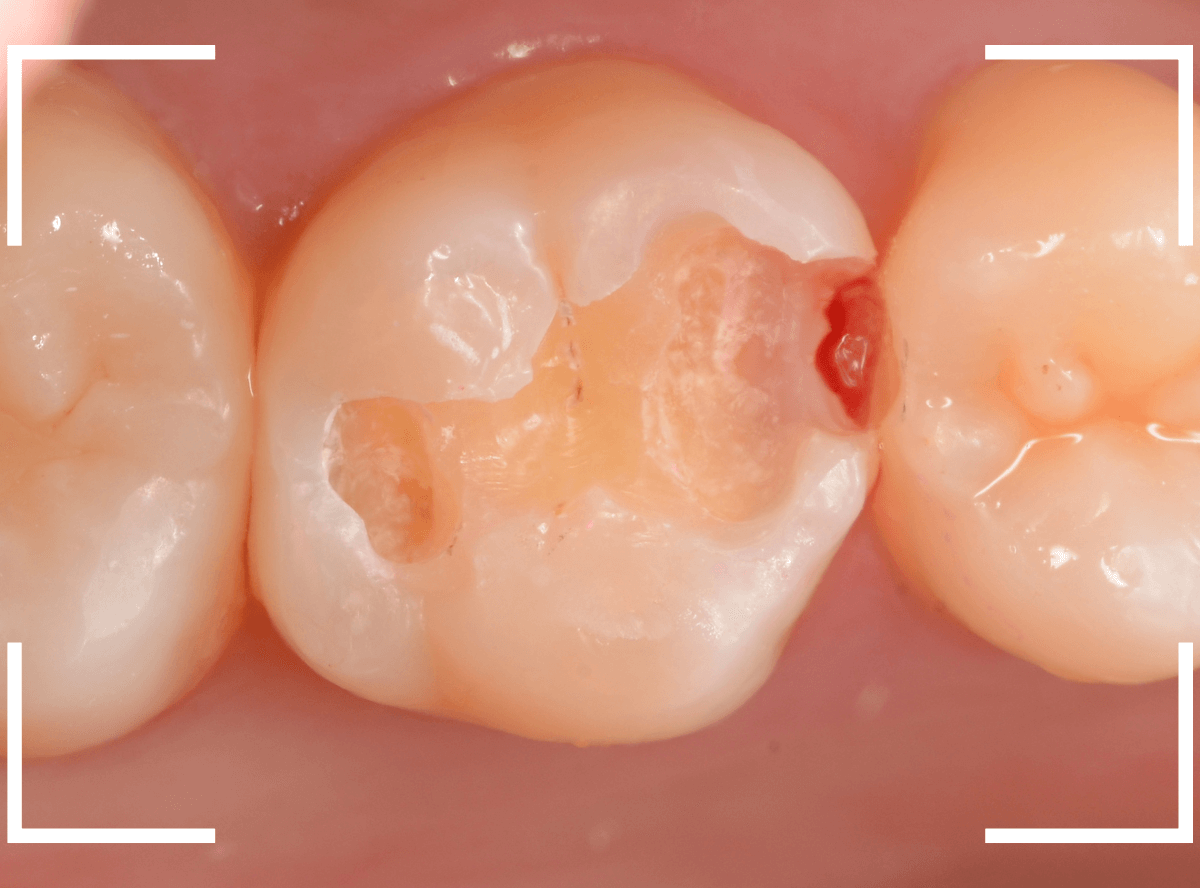

レジンを除去して虫歯をすべて治療したところです。

レジンの中も全体にうっすらと虫歯になっていました。

このくらいの虫歯でも、患者さんは自覚症状はありませんでした。

ご自身の自覚症状だけでは、虫歯の状況がわからないですし、自然に虫歯が治る事もありません。